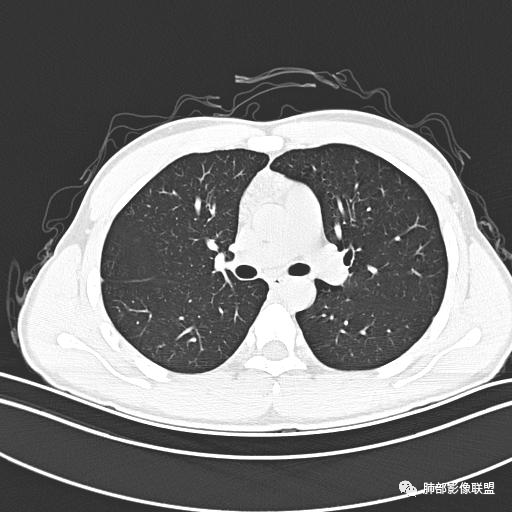

小强:青年,发热,皮疹;双肺散在结节,周围磨玻璃,点晕征,疱疹病毒感染,鉴别荚膜组织胞浆菌,结核。 大雄:青年,急性起病,发热伴全身皮疹2天,抗病毒治疗体温有下降。双肺随机分布大小不等类圆结节,“点晕征”。考虑水痘-疱疹病毒(VZV)血播询问接触史,查体皮疹分布以及形态基本可诊断。 王开金江津中心医院呼吸科:青年男性,起病急,病程短,以发热,皮疹为首发症状,感染指标以单核细胞升高为主,胸部ct双肺多发结界,周围有晕,点晕表现,随机分布,同意於老师意见,水痘疱疹病毒血流感染累及肺。 王秀仙:双肺多发大小不等结节,周围有晕,边缘模糊,呈点晕征表现。青年,急性起病,发热伴全身皮疹2天,抗病毒治疗体温有下降。考虑疱疹病毒。鉴别荚膜组织胞浆菌。 傅昌瑜:19岁男性,发热、全身皮疹2天,单核细胞增高,双肺多发结节,结节边缘见边界不清磨玻璃影。点晕征+发热、全身皮疹+单核细胞增高——考虑水痘-带状疱疹病毒肺炎。 一切∮随缘:年轻男性,发热,皮疹两天,实验室,CRP,PCT增高,影像:双肺多发散在磨玻璃结节,边界欠清,大小不等,呈点晕征改变,以血管束周围分布为主,局部血管束略增粗,其它无明显改变,考虑:1:病毒性肺炎(水痘疱疹病毒?不知道皮肤有无改变)2:真菌(组织胞浆菌,血管侵袭性肺曲霉)3:GPA4:寄生虫(实验室没有看到嗜酸细胞增高) 赵山河:双肺散在结节,周围有晕,边缘模糊,呈点晕征表现。青年,急性起病,发热伴全身皮疹2天,抗病毒治疗体温有下降。考虑水痘—疱疹病毒感染。洪桥爱:青年男性,发热、皮疹2天,伴瘙痒,皮疹于面部首发,之后进展至全身,虽然没有对皮疹进行描述,但是从出疹时间及皮疹进展情况,伴瘙痒,应该就是个水痘患者;CT提示双肺随机分布结节影,部分结节伴有边界不清晕征,考虑水痘血播肺。 刘强:年轻男性,急性起病,皮疹,发热,抗感染治疗体温下降,说明有效。影像表现为散在点晕征,感染类疾病谱(疱疹病毒,真菌,结核),结合年龄,皮肤皮疹,考虑水痘-疱疹病毒性肺炎。 小兜:男性,19岁,发热皮疹两天,颜面部至全身,CRP,降钙素及单核增高。CT示双肺散在小结节,周围伴磨玻璃影,点晕征,考虑为水痘-带状疱疹病毒(varicella-zoster virus,VZV)肺炎 必有路:青年,皮疹+发热+“点晕征”→水痘-疱疹病毒(VZV) 许慧良:青年男性患者,发热、皮疹2天,体温最高38.5℃,第3天皮疹扩展至全身,伴瘙痒,胸部CT:双肺多发随机分布的小结节,结节周边见边界模糊的晕征,考虑水痘病毒感染流心明智:男,19,急性起病,发热伴全身皮疹2天。出疹顺序头→全身,抗病毒有效。胸部CT:两肺多发大小不等类圆形实性小结节影,随机分布,结节周围环绕GGO,边界模糊,呈点晕征。出疹特点是关键,未提示。考虑:血播病毒性肺炎,水痘-疱疹病毒?麻疹?鉴别荚膜组织胞浆菌、TB、血管炎、寄生虫等。 浪迹天涯:病灶多为5-10mm大小结节,结节周围可见磨玻璃样的晕环,常多发,可分布于肺内任何区域,考虑水痘—带状疱疹病肺炎如果短时间内有新的一个区域浸润,更加能说明,